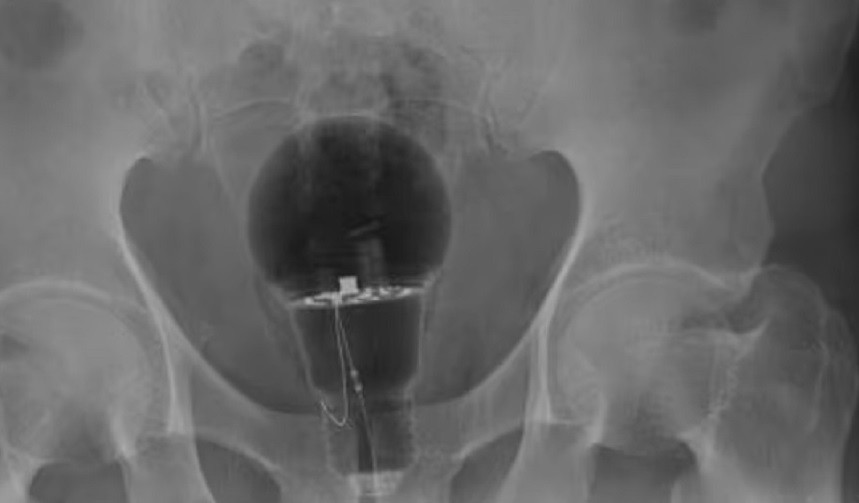

Μεγάλη έκπληξη προκάλεσε σε γιατρούς νοσοκομείου της Κολομβίας όταν τους επισκέφθηκε εσπευσμένα ασθενής καθώς ένας λαμπτήρας είχε σφηνώσει στον πρωκτό του. Ο 53χρονος άνδρας του οποίου η ταυτότητα παρέμεινε μυστική, δημοσίευσε η βρετανική εφημερίδα «Daily Mail», πήγε φέτος σε τοπικό νοσοκομείο και παραπονέθηκε για έντονο πόνο στο σημείο. Οι γιατροί δεν είδαν τίποτα κατά τη διάρκεια της φυσικής εξέτασης, αλλά σοκαρίστηκαν όταν μια ακτινογραφία αποκάλυψε μια μεγάλη λάμπα «κολλημένη» στον πρωκτό του. Η υπόθεση, δε, έγινε γνωστή όταν έγραψε γι’ αυτή στο διαδίκτυο ο γαστρεντερολόγος, Χουλιάν Πιλόρι. Δεν είναι σαφές πώς βρέθηκε εκεί ο λαμπτήρας, αφού ο άνδρας προτίμησε να μην τους πει, εν

Δεν μπορούσαν να πιστέψουν στα μάτια τους οι γιατροί σε νοσοκομείο της Κολομβίας όταν διαπίστωσαν ότι ασθενής είχε έναν λαμπτήρα σε πολύ ευαίσθητο σημείο του σώματος του. Σύμφωνα με την Daily Mail, ο 53χρονος πήγε στο νοσοκομείο και είπε στους γιατρούς ότι είχε τρομερούς πόνους στο συγκεκριμένο σημείο. Στο πρώτο στάδιο της φυσικής εξέτασης, οι […] Κολομβία – Σάλος στα επείγοντα: 53χρονος ασθενής πήγε με μια λάμπα σε ευαίσθητο σημείο του σώματος του - olympia